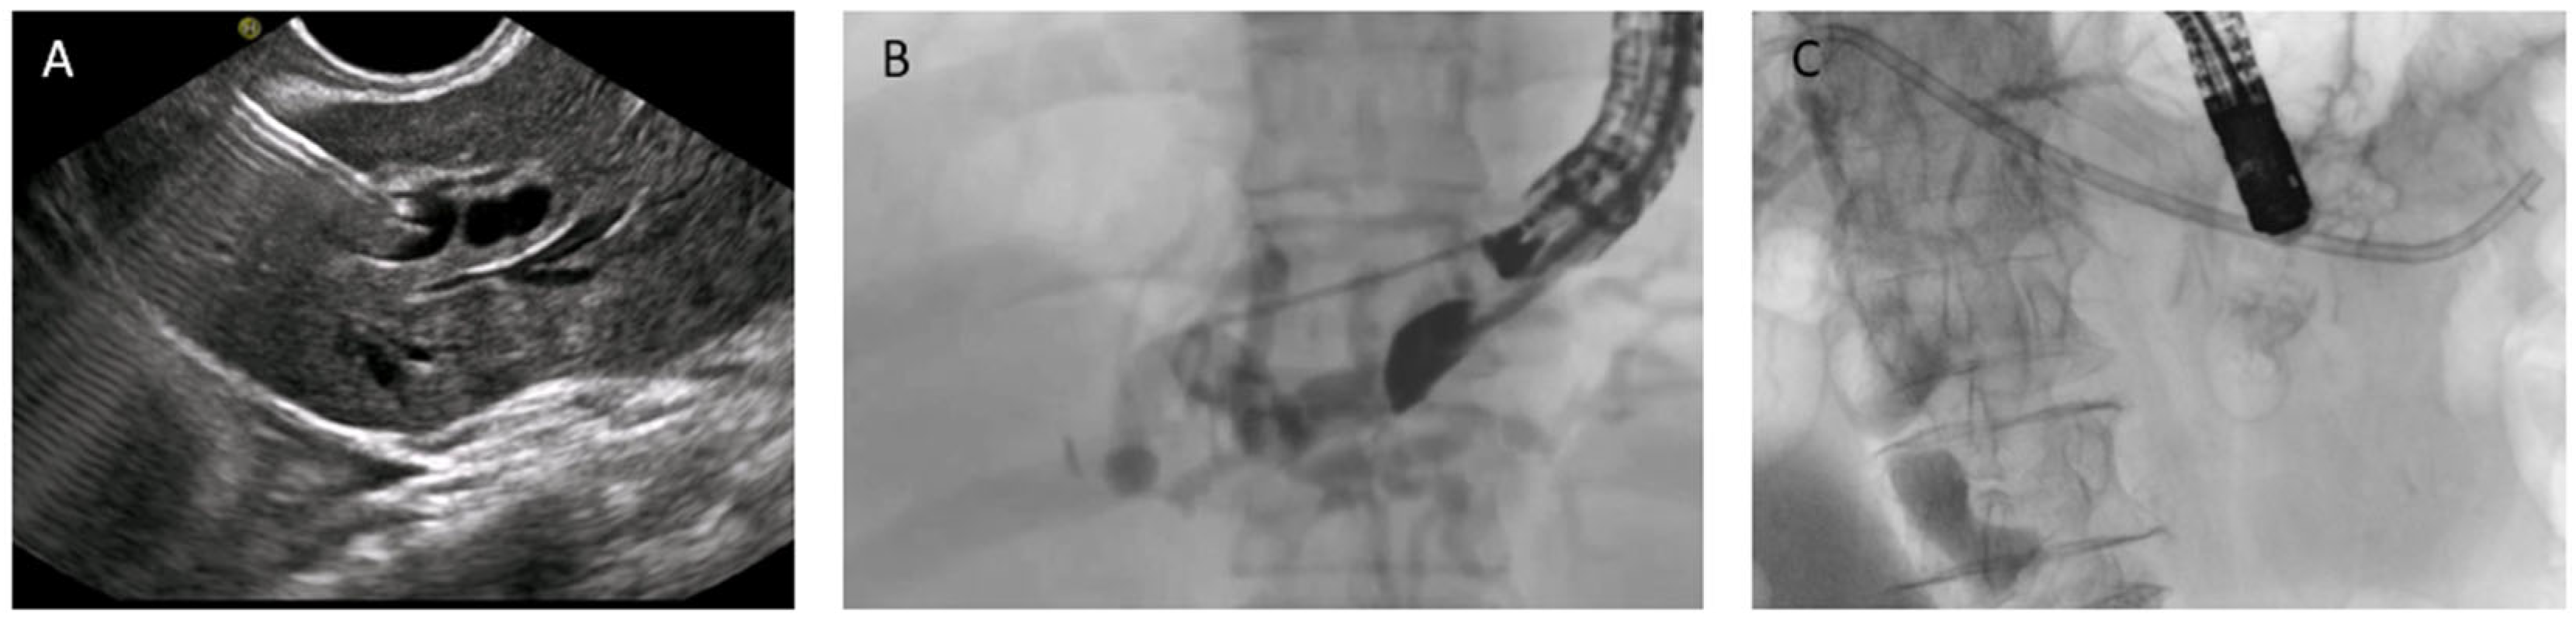

Figure 9. EUS-guided duodenojejunal anastomosis (EDEE): (A) EUS-guided deployment of a LAMS into the jejunal lumen; (B) use of a pediatric colonoscope to reach the biliojejunal anastomosis through the LAMS (indicated by the green arrow); (C) fcSEMS protruding from the anastomosis.

In 2014, the first case of a trans-enteric duodeno-jejunal bypass by using a lumen-apposing metal stent (LAMS) to facilitate biliary access in Roux-en-Y hepaticojejunostomy was published [54]. To date, after more than ten years, EDEE is a consolidated and well-documented technique that represents a valid therapeutic option in patients with altered anatomy, although relegated to tertiary referral centers with experience in this type of procedure.

In this technique, a LAMS is used to create an anastomosis between the stomach or duodenum and the afferent biliary limb, thus restoring endoscopic access to the biliary anastomosis with a standard duodenoscope.

By providing a permanent and reusable access route, the entero-enteric bypass enables repeated interventions over time with standard devices. Moreover, the possibility to reach directly the anastomotic area with large-caliber scopes (e.g., pediatric colonoscope with 3.8 mm operative channel) also permits treatment of the most challenging cases with the full standard equipment (Figure 9).

The largest case series published, and subsequent expanded follow-up, report a technical success above 95% and long-term clinical efficacy above 90%. AEs included stent migration, bleeding, and leaks but were largely manageable. Compared with EA-ERCP, entero-enteric bypass is more durable and facilitates reintervention; compared with PTBD, it avoids external drains and improves quality of life [55,56].